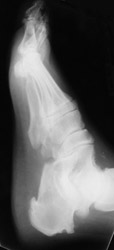

Ankylosing Spondylitis: Erosions of 5th MT headAnkylosing Spondylitis: Lateral- Broad base calcaneal spur and erosion of the calcaneusAnkylosing spondylitis (AS) is a HLA-B27 spondyloarthropathies which is characterized by bony ankylosis and syndesmophyte formation.

Erosion pattern:

Erosions are usually superficial, with productive response. Intra-articular ankylosis occurs in a short period of time.